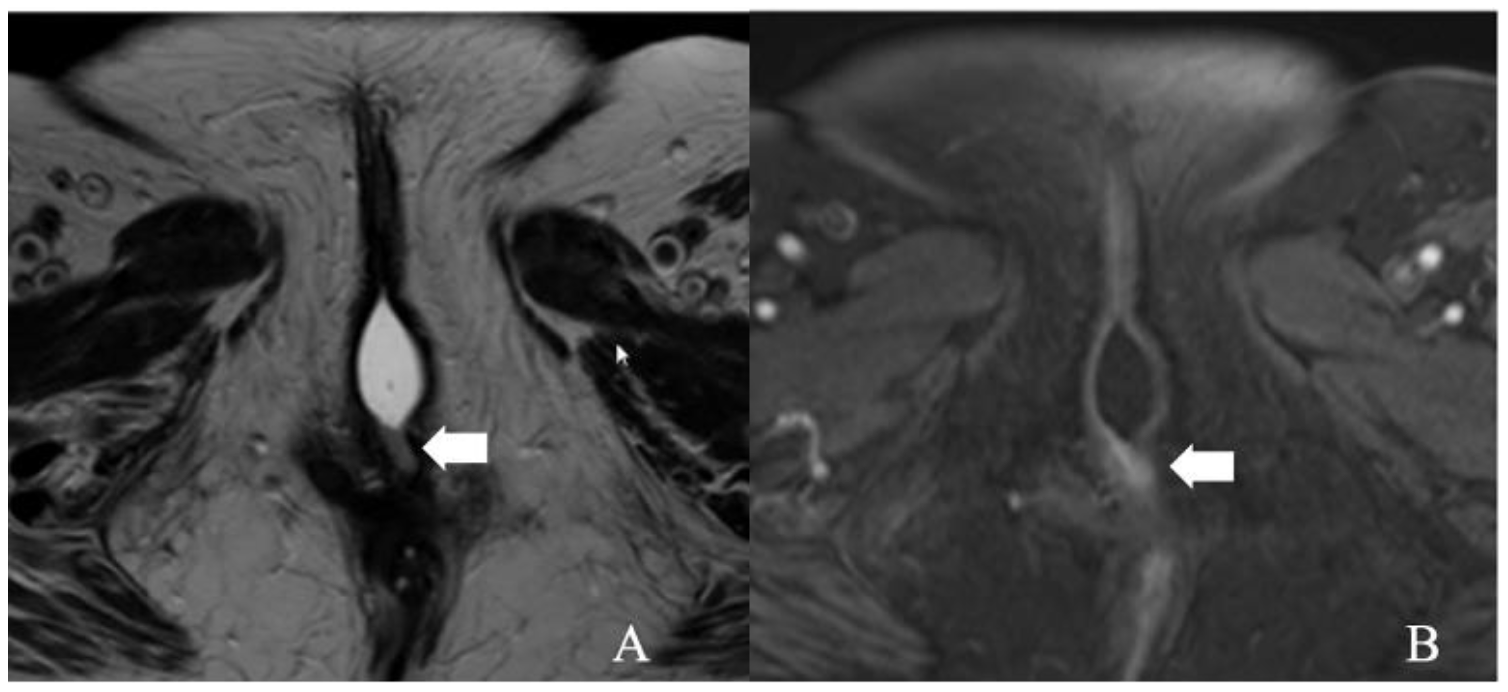

5.1. Stage I

5.2. Stage II